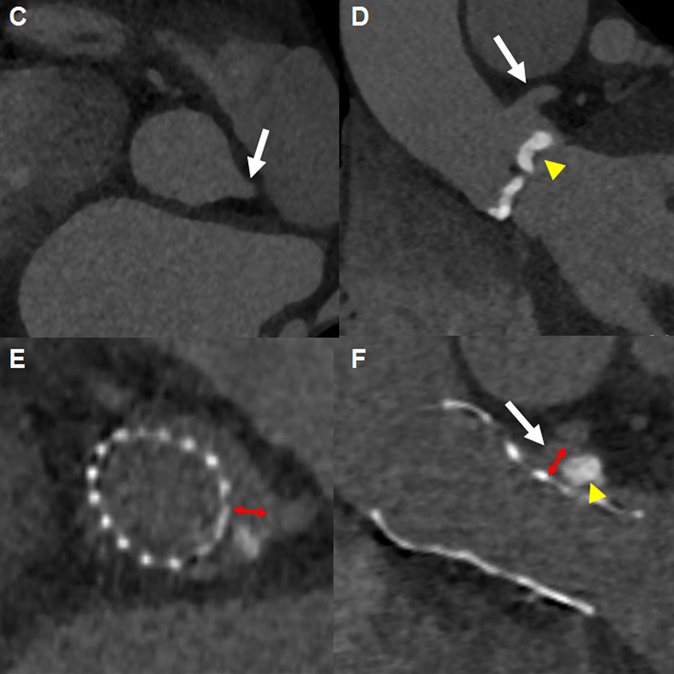

스탠포드 대학교의 메디컬센터는 FAME 연구의 저자인 William Fearon이 있는 곳이기도 합니다. 저의 주된 관심 분야는 경피적 대동맥판막치환술(TAVR)에 대한 것이고 시술을 주로 Alan C. Yeung 선생님과 William Fearon 선생님이 주로 하셨습니다. 매주 금요일 아침 방사선과 회의실에서 심장내과, 흉부외과, 마취과, 방사선과, 코디네이터 선생님이 모여서 케이스에 대한 토의하고 시술 방법, 시기 등을 조율 하였습니다. 이러한 팀 회의에 참석하며 여러 선생님들의 의견을 듣는 것이 도움이 많이 되었고, 특이한 점은 흉부외과 선생님들도 TAVR 시술을 같이 하고 있었습니다. CT 측정하시는 선생님 통해서 pre-TAVR CT evaluation 하는 과정을 배웠으며 이는 이후 연구는 물론이고 지금도 케이스 선별과정을 진행하는 데 있어서 큰 밑거름이 되고 있습니다. 인상 깊은 한 케이스는 그림 1에서와 같이 판막에 심한 석회화가 관찰되어 시술 시 관상동맥폐색의 위험성이 높다고 판단 되었지만 TAVR 시술 이후 판막이 옆으로 접히듯이 밀려난 예로 실제로는 관상동맥 폐색의 위험성 보다는 annular rupture의 위험이 더 컸었을 것으로 보입니다.

[그림 1] The displacement movement of heavy calcified leaflet after deployment of a 29 mm Evolut R valve (Int J Cardiol Heart Vasc 2021;30:100917)